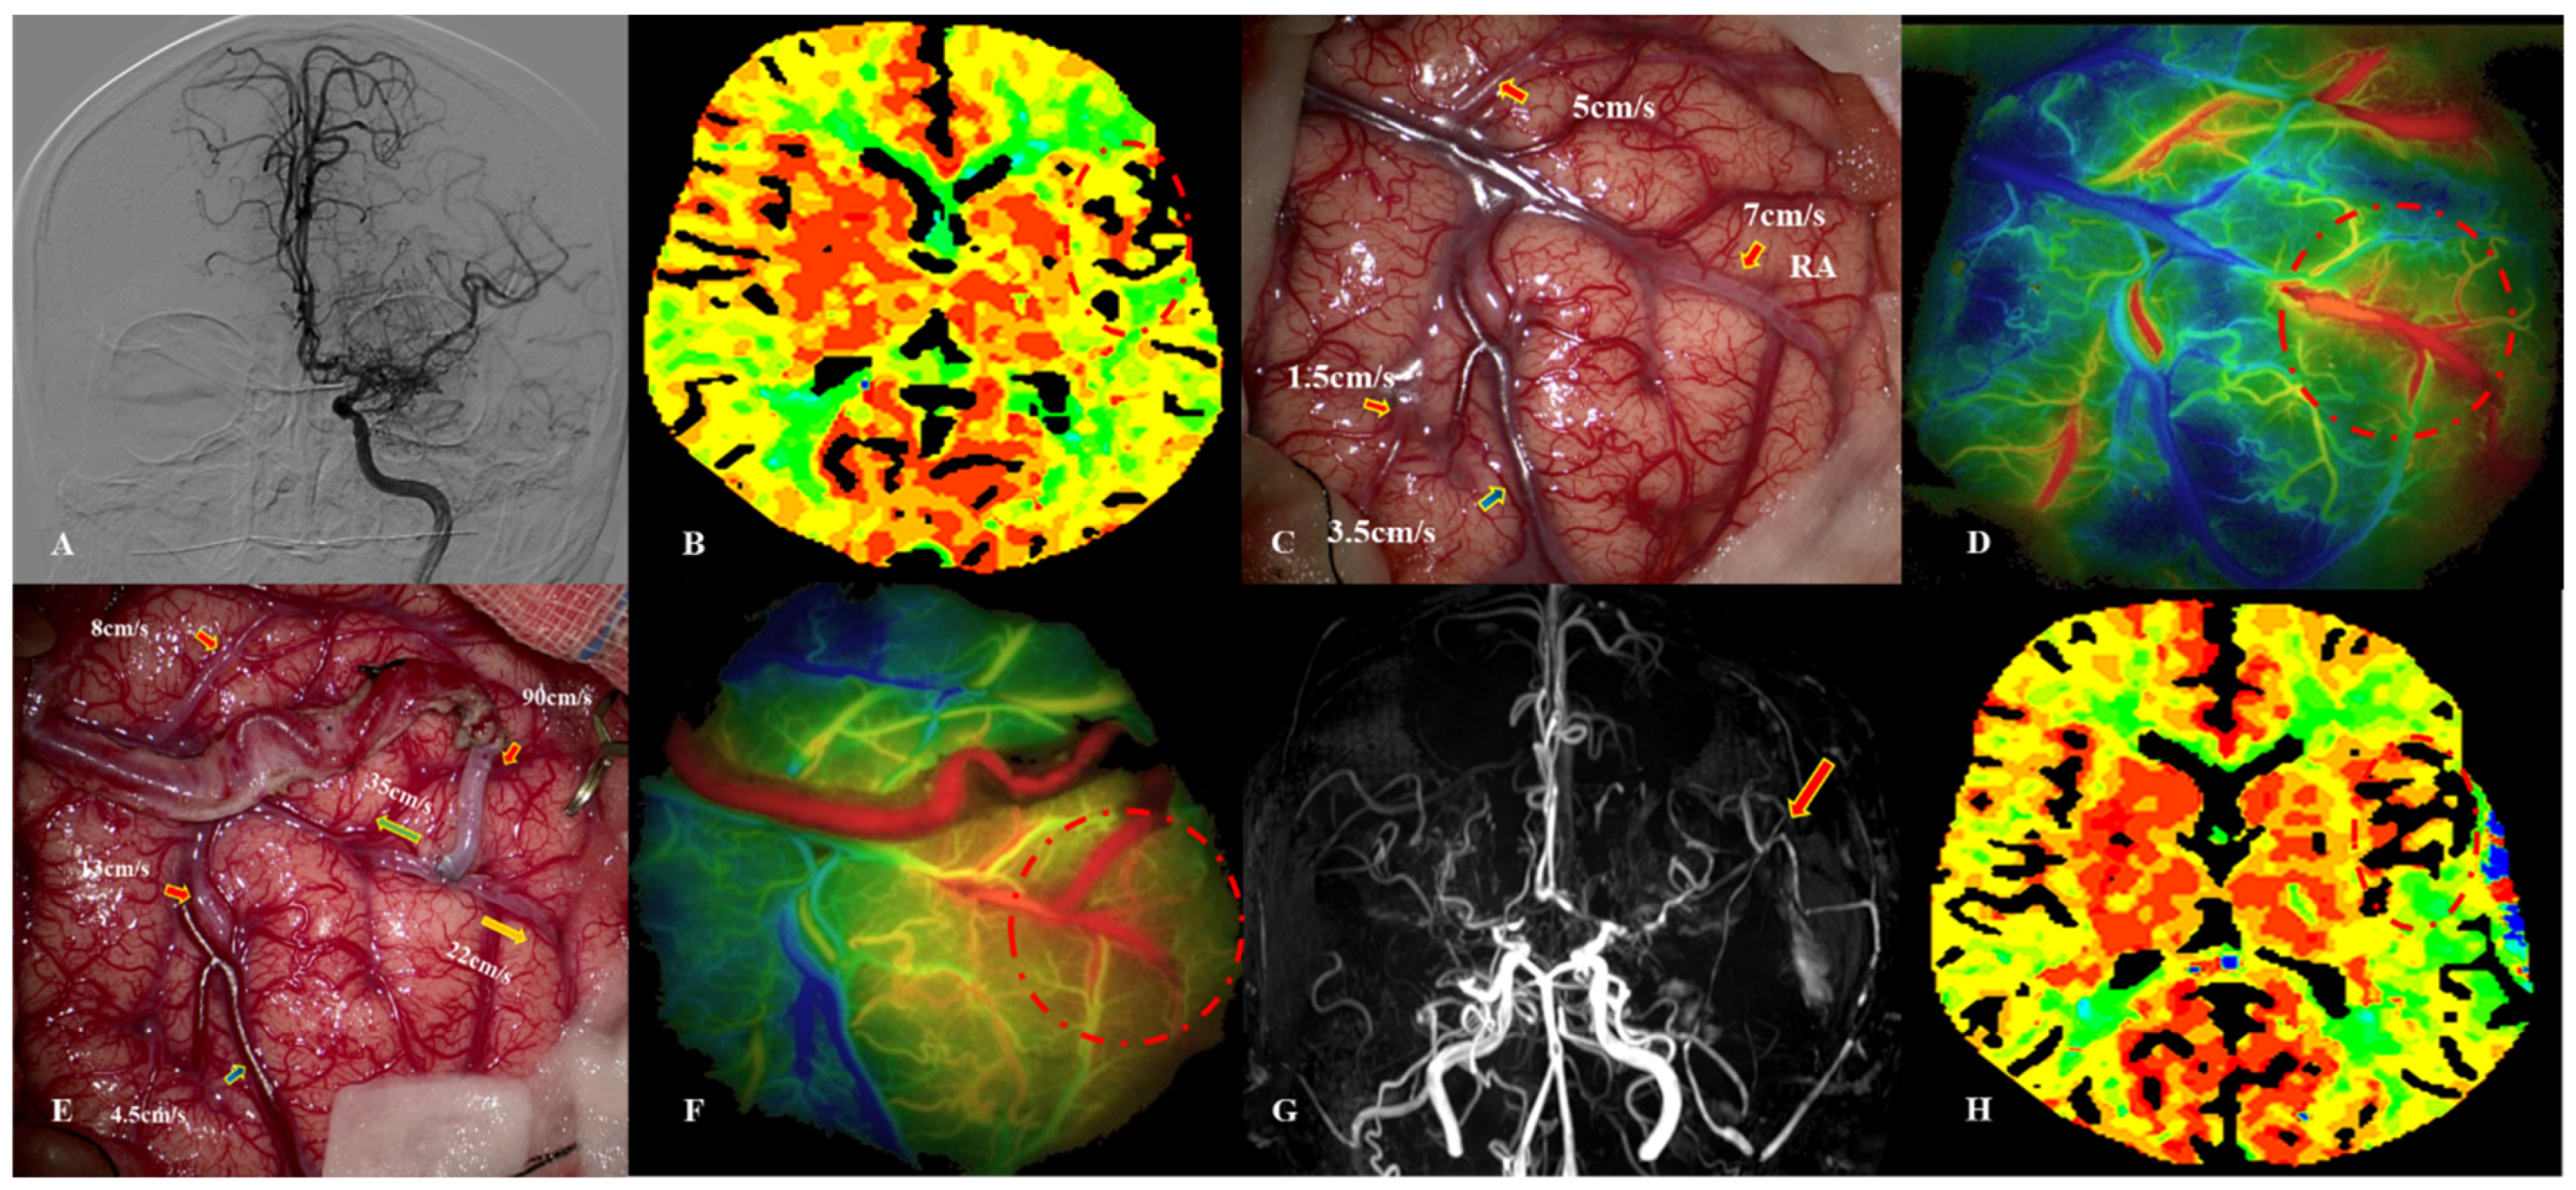

5.2. MDU Findings in Cases with CHS

- Yang, D.; Zhang, X.; Tan, C.; Han, Z.; Su, Y.; Duan, R.; Shi, G.; Shao, J.; Cao, P.; He, S.; et al. Intraoperative transit-time ultrasonography combined with FLOW800 predicts the occurrence of cerebral hyperperfusion syndrome after direct revascularization of Moyamoya disease: A preliminary study. Acta Neurochir. 2021, 163, 563–571. [Google Scholar] [CrossRef]